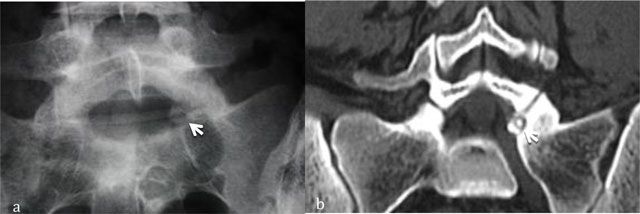

Figure 1

Osteoid osteoma of L5. Radiograph (a) shows focal lucency in the neural arch. CT scan (b) shows the calcified nidus (arrow).